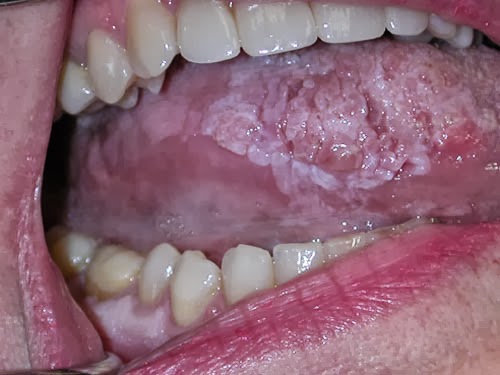

Cáncer oral 😈

Cancer oral 😈

Cáncer Oral | Campaña Precoz Cáncer Oral 😈